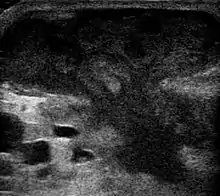

They are usually caused by a bacterial infection.[8] Often many different types of bacteria are involved in a single infection.[6] In many areas of the world, the most common bacteria present is methicillin-resistant Staphylococcus aureus.[1] Rarely, parasites can cause abscesses; this is more common in the developing world.[3] Diagnosis of a skin abscess is usually made based on what it looks like and is confirmed by cutting it open.[1] Ultrasound imaging may be useful in cases in which the diagnosis is not clear.[1] In abscesses around the anus, computer tomography (CT) may be important to look for deeper infection.[3]

An abscess is a localized collection of pus (purulent inflammatory tissue) caused by suppuration buried in a tissue, an organ, or a confined space, lined by the pyogenic membrane.[25] Ultrasound imaging can help in a diagnosis.[26]